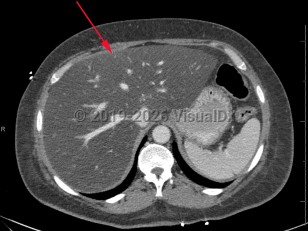

Metabolic dysfunction-associated steatotic liver disease

Screening for MASLD is of the utmost importance in patients with underlying risk factors, primarily obesity and metabolic syndrome, as it is often asymptomatic. American Diabetes Association (ADA) guidelines recommend routine MASLD screening in patients with diabetes and prediabetes. Some patients report vague symptoms such as fatigue or mild right upper quadrant abdominal pain. If MASLD progresses to cirrhosis, patients will often present with signs and symptoms of advanced liver disease: spider angiomata, gynecomastia, ascites, jaundice, and peripheral edema. Cardiovascular disease is the leading cause of death in persons with MASLD.

The primary risk factors for MASLD are central obesity, type 2 diabetes mellitus, and hyperlipidemia. Modification of these risk factors, mostly through weight loss and dietary and lifestyle changes, is the most effective preventive and treatment strategy.